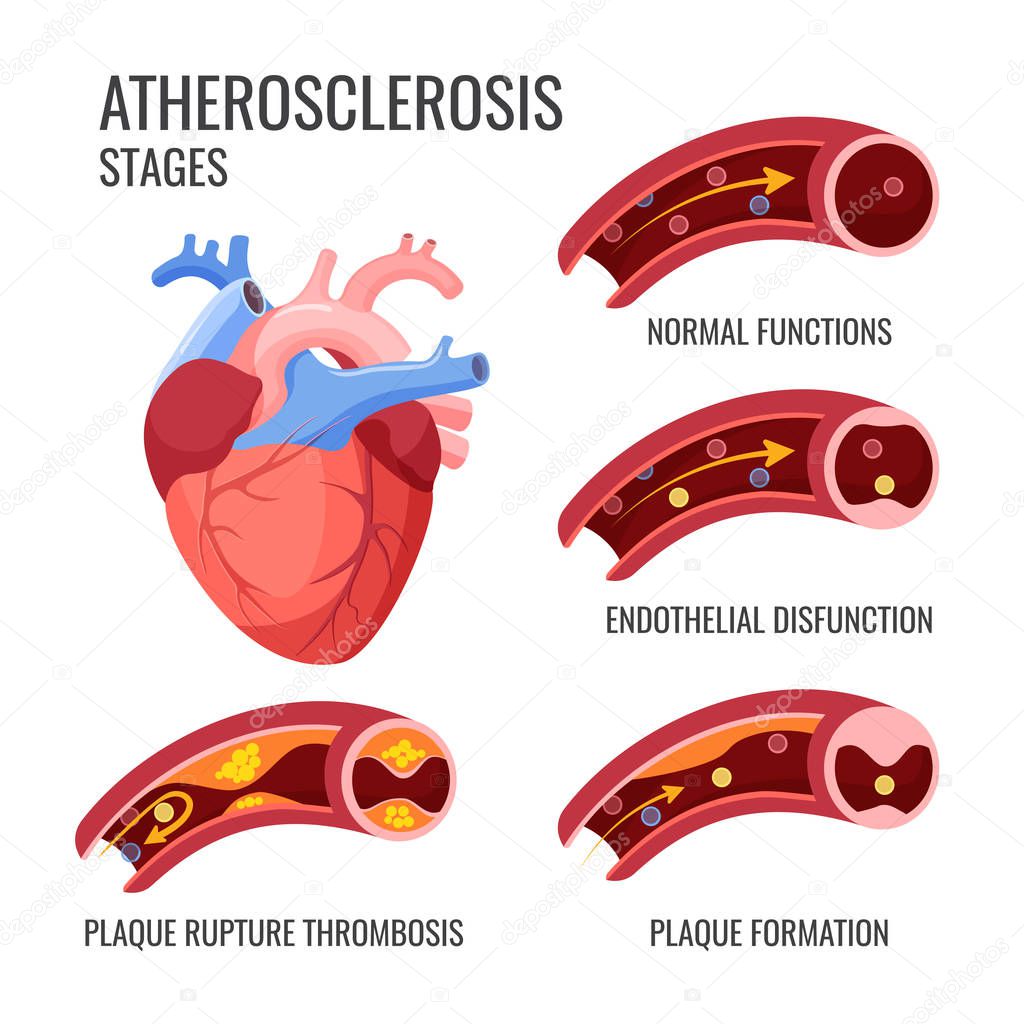

Atherosclerosis Stages: Healthy Artery, Plaque Formation, and …

Atherosclerosis stages. Normal functions, endothelia disfunction …

Stages of atherosclerosis Stock Vector Image by ©edesignua #144301487